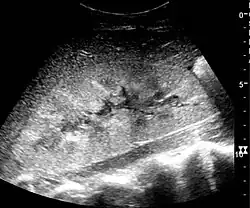

In medical imaging, the acute changes in the kidney are often examined with renal ultrasonography as the first-line modality, where CT scan and magnetic resonance imaging (MRI) are used for the follow-up examinations and when US fails to demonstrate abnormalities. In evaluation of the acute changes in the kidney, the echogenicity of the renal structures, the delineation of the kidney, the renal vascularity, kidney size and focal abnormalities are observed.[20] CT is preferred in renal traumas, but US is used for follow-up, especially in the patients suspected for the formation of urinomas. A CT scan of the abdomen will also demonstrate bladder distension or hydronephrosis.[21]

Renal ultrasonograph in renal failure after surgery with increased cortical echogenicity and kidney size. Biopsy showed acute tubular necrosis.[20]